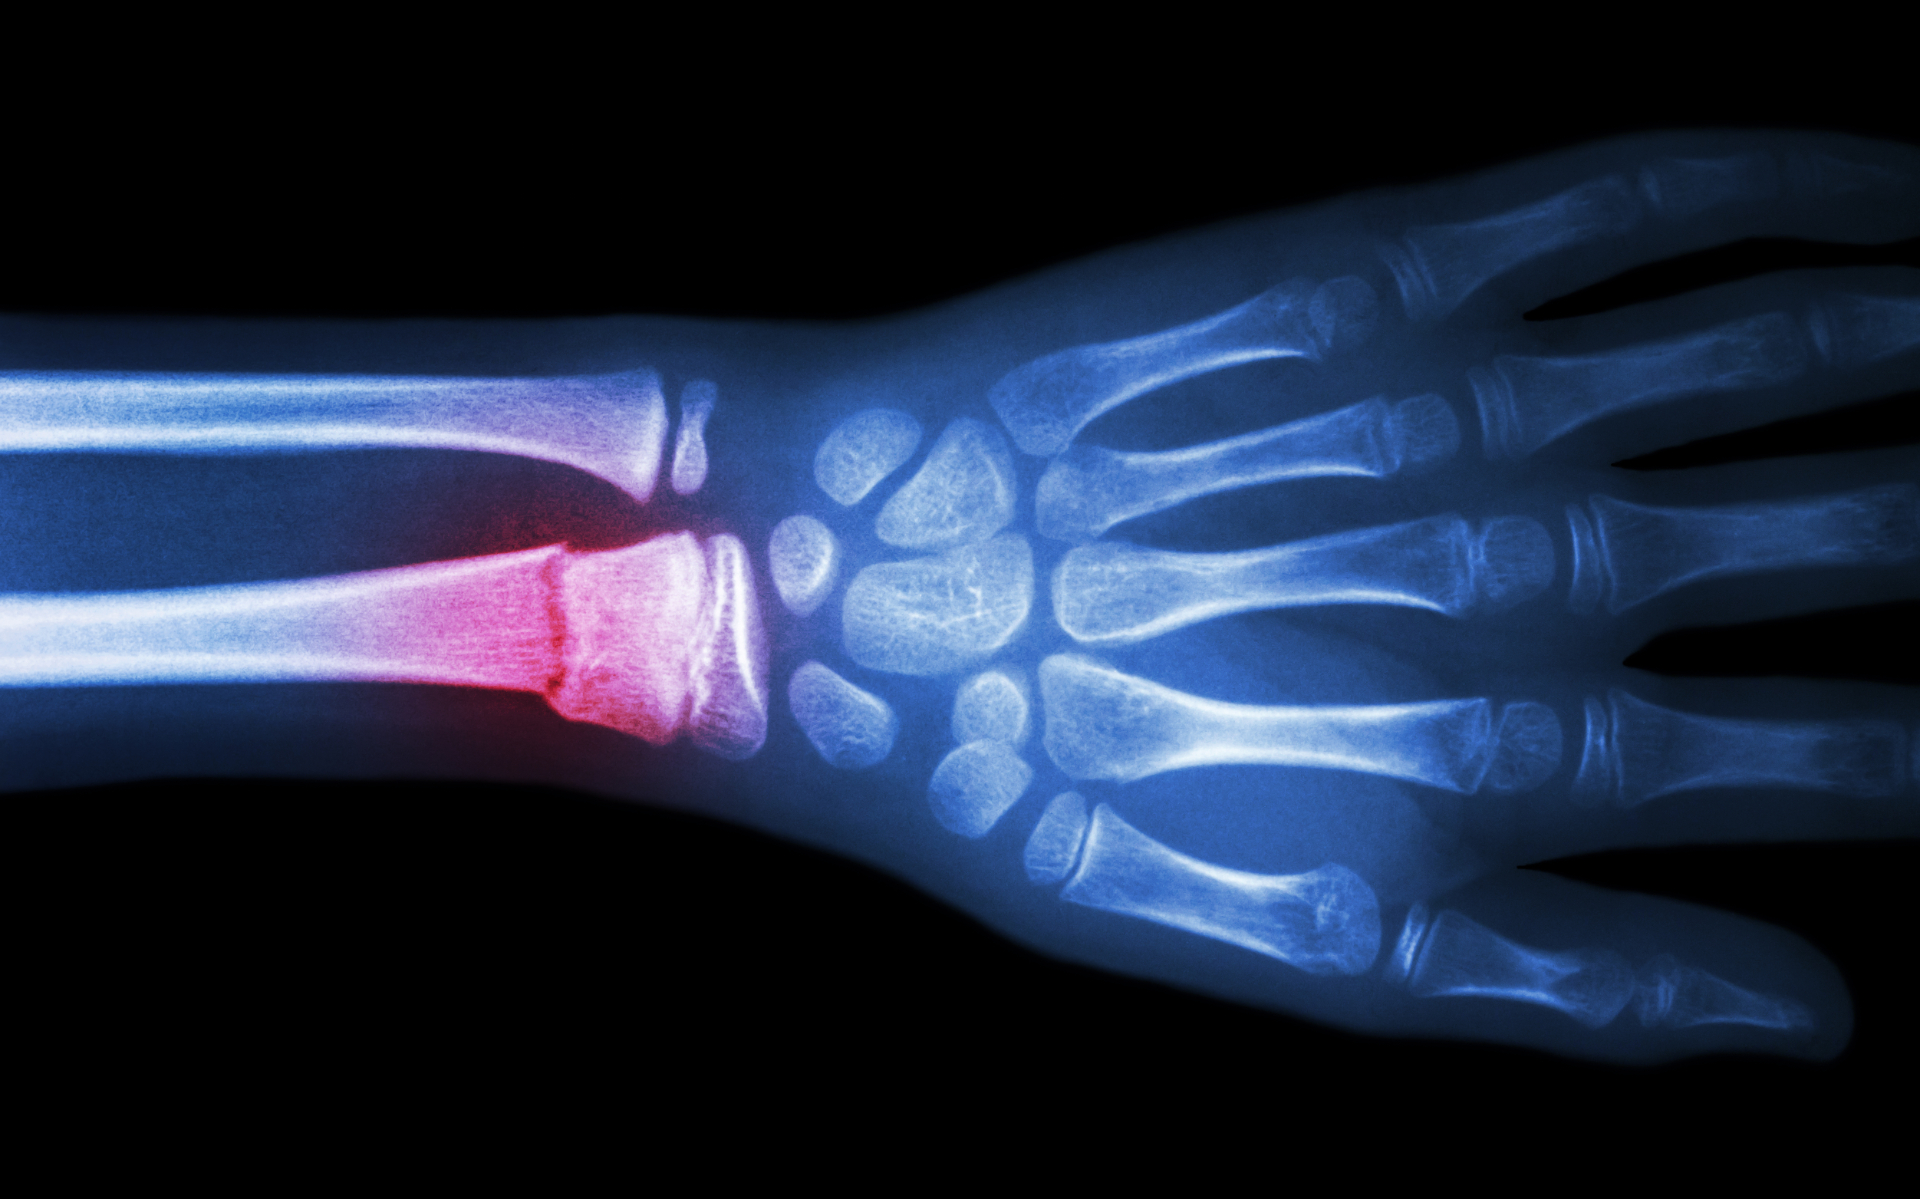

Radiografía articular

• Rayos X: para observar articulaciones, huesos y fracturas.